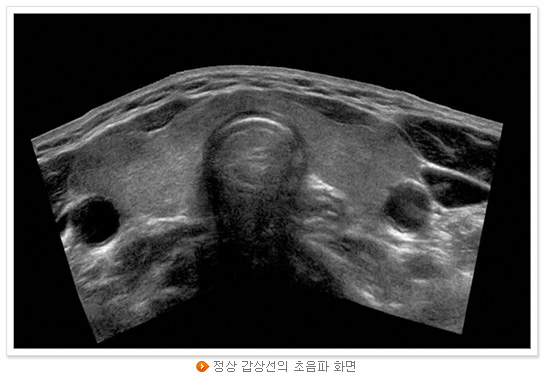

대부분의 경우 아무런 증상이 없고 혈액검사로도 갑상선암인지 아닌지 구별할 수 없다. 단 갑상선 수질암에서는 혈액 내 특정 종양표지자가 상승하지만 우리나라에서 수질암의 빈도는 매우 낮다. 우리나라에서 가장 흔하고 예후도 가장 좋은 갑상선 유두암의 경우 초음파검사에서 몇 가지 특징적인 소견을 보이므로 갑상선 혹이 발견되면 반드시 초음파검사를 통해 혹의 위치와 크기, 그리고 갑상선암일 때 보이는 소견이 있는지 확인하여야 한다. 혹의 크기가 1cm보다 큰 경우, 또는 1cm보다 작더라도 갑상선암이 의심되는 소견이 있으면 ‘미세침흡인 세포검사’를 하여 양성 결절인지 아니면 악성 결절(갑상선암) 인지를 감별해야 한다. 그러나 5mm보다 작은 혹의 경우에는 설사 암이라고 하여도 림프절 전이 가능성도 낮고 또 미세침흡인 세포검사에서 세포가 적게 나와 진단을 못 내리게 될 가능성이 증가하므로 최근에는 5mm보다 큰 경우에만 미세침흡인 세포검사를 하는 추세이다.